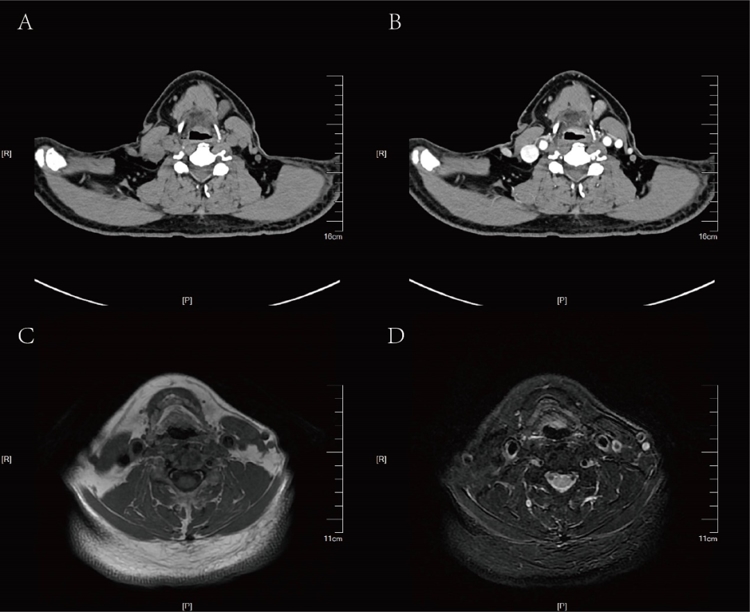

患者为61岁男性,因“咽部疼痛2个月”来吉大二院头颈外科就诊。电子喉镜检查发现会厌喉面病变(图1)。喉部影像学结果提示会厌喉面占位性病变(图2)。病理结果为喉恶性肿瘤。

▲图2:术前喉CT平扫+增强(A,B)及喉MRI平扫(C,D)